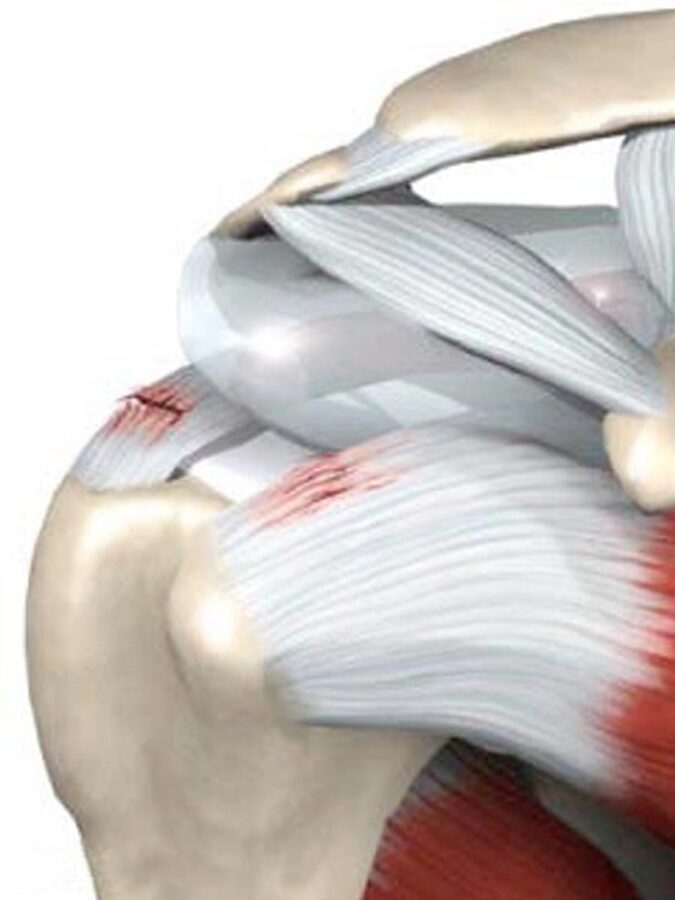

El manguito rotador está conformado por cuatro tendones profundos, por debajo del deltoides, que se insertan en el humero. Estos son: el supraespinoso (arriba), el subescapular (delante), infraespinoso y redondo menor (por detrás).

Estos tendones con el sobreuso o mal uso, así como con el paso del tiempo van desgastando y comienzan a romperse cerca de su inserción en el humero. Habitualmente el supraespinoso es el que se afecta (>80%) seguido por el infraespinoso y el subescapular.

Estas lesiones habitualmente afectan a personas mayores a los 50 años aunque ocasionalmente pueden observarse en personas más jóvenes vinculadas a traumatismos. Las lesiones pueden ser parciales o completas, independientemente de la magnitud todas pueden generar dolor. Ero cuando las rupturas son completas además del dolor comienzan a generar debilidad e impotencia funcional. Desafortunadamente en este tipo de lesiones, como muchas otras, no pueden ser reparadas por el organismo por lo que sino podemos aliviar los síntomas con la fisioterapia debemos realizar una intervención para unir nuevamente el tendón al hueso.